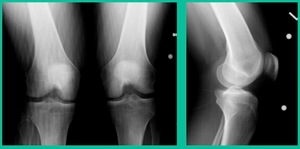

43-Year-Old, symptomatic medial femoral condyle.

D1 football player formally, affecting ADLs. For this one, I initially just wanted to watch it. This looks pretty small when he came in. Let’s see what happens. Six months later, this is where he progressed to.

We get in there, it’s delaminated, not much bone, nothing to fix in my mind, and so we drilled it.

How do these do? There’s actually reasonable data for marrow stimulation for OCD. But if you have the option for small defects, I would prefer an osteochondral allograft over microfracture based on the literature. That’s the take-home. Marrow stimulation, if you do it, you’re probably better off drilling it. We showed that we could reduce revision rates with marrow stimulation by two-thirds if you drill it versus use a microfracture awl.